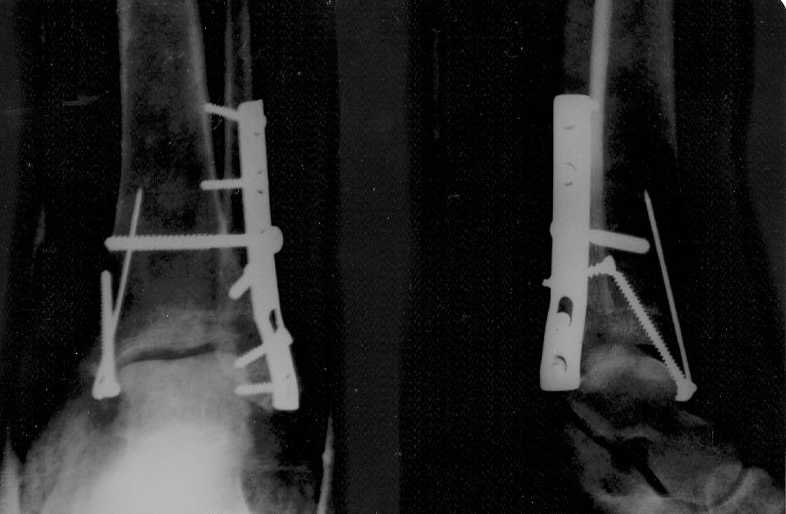

закритий двухкисточковыйп ерелом косточек правой голени с смещением,и частичное повреждение дистального межголеньего синдесмоза с подвывихом ступнин

1 неделя гипс,повторный снимок,направление на операцию,через неделю операция,гипс 8 недель,сняли 3 дня назад , вставать не в состоянии,двигать ступней тоже нереально....

нога отекла ,как у слона , подскажите правильно ли все сделано , нормальное ли состояние на сегоднешний день, и сколько нужно времени, чтобы ходить хотя бы с палочкой, какие упражнения? врач сказал: массаж не нужно, парить только ногу и потехоньку ее нагружать..снимок прилагаю

Проблем больших не видно. Нужно разрабатывать движения. В качестве образца - здоровая нога. Надо именно разрабатывать. Частичная нагрузка возможна. Будете ее увеличивать по мере спадения отека.